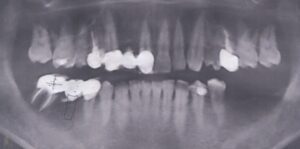

- アングルクラスⅠであった。

- アングルクラスⅠで上下顎臼歯部に不適合な修復・補綴が見られ、

- クリーニングの後、上下顎臼歯部にセラミックインレー・アンレー・インプラントを装着した。

審美的な仕上がりで、患者自身も満足した。3年経過し良好である。

- 現在は2〜3ヶ月おきのメインテナンス中である。